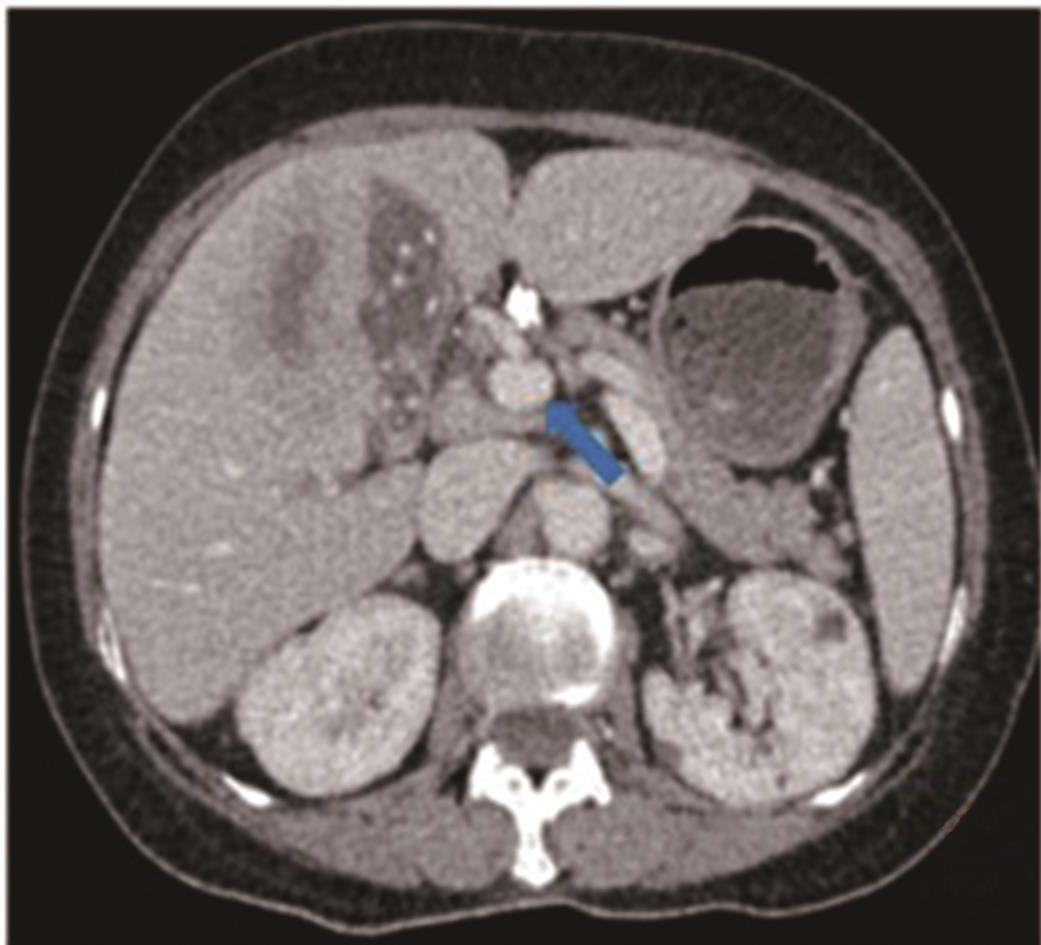

• 探讨增强CT在鉴别胆囊癌侵犯肝脏与肝癌累及胆囊病变中的应用价值

摘要:目的 探讨增强电子计算机断层扫描(computer tomography,CT)在胆囊癌侵犯肝脏与肝癌累及胆囊病变中的鉴别诊断价值。方法 收集2012年2月到2022年2月重庆医科大学附属第一医院115例患者临床及影像学资料,其中胆囊癌侵犯肝脏病例69例,肝癌累及胆囊病例46例,记录性别、年龄、肿瘤大小、肿瘤边界、胆囊形态、肝硬化、胆管扩张、肿瘤内或胆管系统内高密度影、门静脉癌栓、强化方式、强化程度、淋巴结肿大及远处转移共13个观察指标,并进行统计学分析。结果 性别(P=0.007)、年龄(P=0.002)、肿瘤大小(P=0.003)、肝硬化(P<0.001)、肿瘤内或胆管系统内高密度影(P=0.013)、门静脉癌栓(P<0.001)、强化方式(P<0.001)及淋巴结肿大(P=0.034)有统计学差异。通过回归分析筛选出年龄(敏感度为0.812,特异度为0.457)、肿瘤大小(敏感度为0.630,特异度为0.696)、门静脉癌栓(敏感度为0.326,特异度为0.957)、淋巴结肿大(敏感度为0.681,特异度为0.522)为显著分类指标,联合4个观察指标的参数绘制受试者工作特征(receiver operating characteristic,ROC)曲线,曲线下面积(area under the curve,AUC)为0.770,敏感度为0.674,特异度为0.826。结论 增强CT在鉴别胆囊癌侵犯肝脏与肝癌累及胆囊病变时,性别、年龄、肿瘤大小、肝硬化、肿瘤内或胆管系统内高密度影、门静脉癌栓、强化方式及淋巴结肿大有鉴别价值,同时结合年龄、肿瘤大小、门静脉癌栓及淋巴结肿大有助于提高鉴别诊断能力。